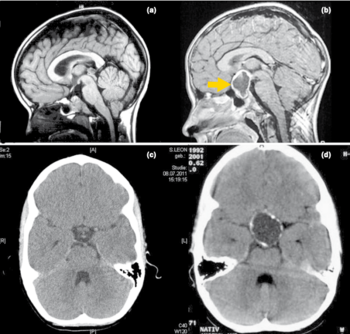

Zur Diagnosestellung und Vorbereitung des operativen Eingriffs werden die Durchführung einer Kernspintomographie (MRT) und meist auch einer Computertomographie (CT) notwendig.

Abbildung: Kernspintomographische (MRT) und computertomographische (CT) Bilder vonKraniopharyngeom-Patienten und Normalbefunde. In der Abbildung ist mit Pfeil im Vergleich zum Normalbefund (a, c) ein zystisches Kraniopharyngeom dargestellt, das im CT (d) Verkalkungen aufweist.